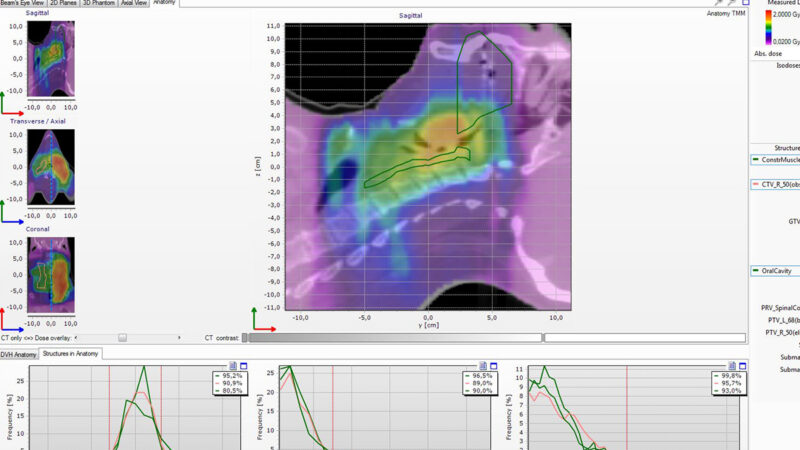

Delta4 software

Streamline your workflow

Delta4 software

Instant and accurate analysis

Delta4 Software

Instant Results